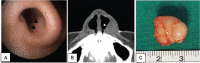

Rationale: Neurilemmoma is a benign tumor derived from the Schwann cells of the nerve sheath. The highest incidence of neurilemmoma occurs in the head and neck region; however, the nose and paranasal sinuses are rarely involved. Less than 4% of these tumors involve the nasal cavity and paranasal sinuses. To date, only six cases of nasal vestibule neurilemmoma have been reported.

Patient concerns: Two patients (a 32-year-old man and a 42-year-old woman) visited our clinic with complaint of a lump in the left nasal vestibule.

Diagnosis: Histopathological examination and immunohistochemical staining confirmed a neurilemmoma.

Interventions: The mass was completely removed via an intranasal approach.

Outcomes and lessons: Neurilemmoma is easy to overlook because it occurs rarely in the nasal vestibule, but neurilemmoma needs to be considered as a differential diagnosis.